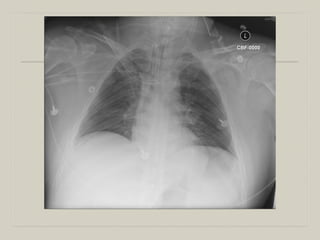

Diagnosis

  Fever

  Purulent Sputum

  Leukocytosis

  Decrease in oxygenation

&

  New or progressive radiographic infiltrates

  Autopsy: 69% Sensitivity; 75% Specificity